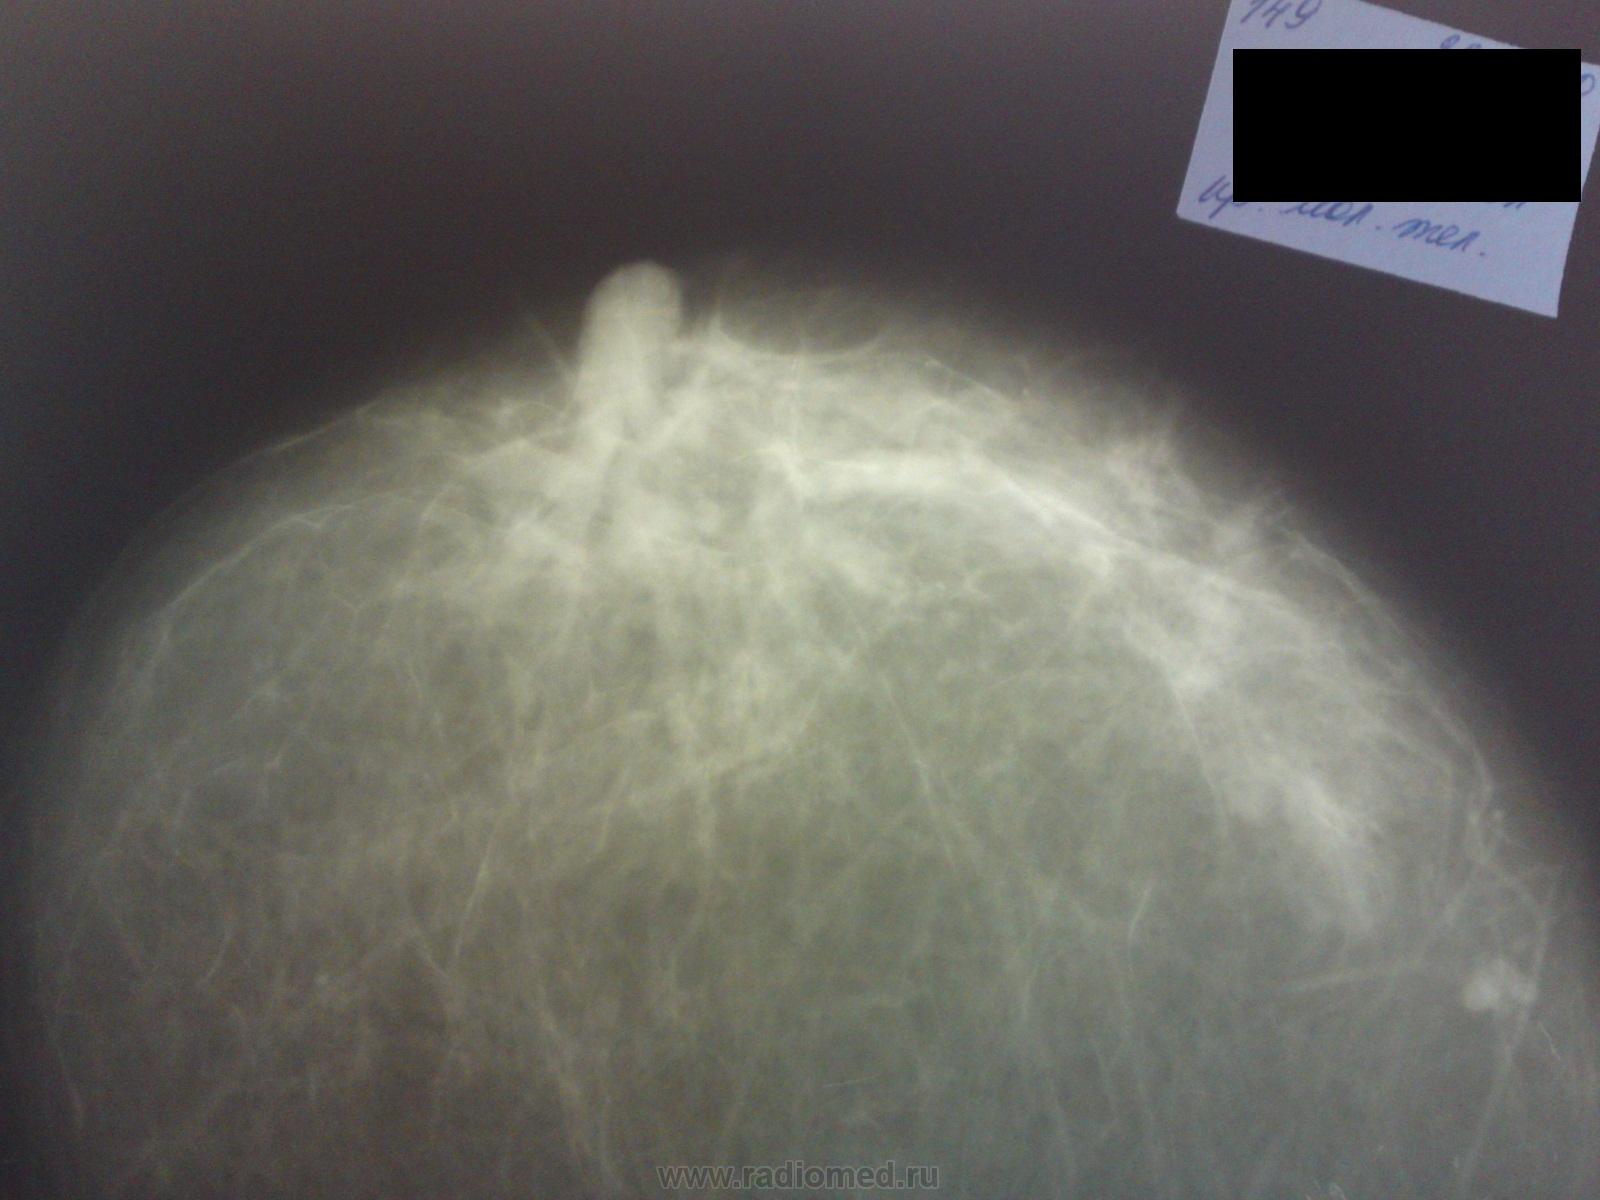

Какого генеза эти тени?

Заключение: Очаговые образования, вероятнее всего доброкачественные . Генез и гистология не наше дело. Отличить кисту от предполагаемой фиброаденомы или др. добра поможет отличить узи.

да мне тоже кажется здесь ничего особенного, фиброаденомы скорей всего...

Думается что тени образют частично гиперплазированные дольки молочных желез, слева в верхне наружном квадранте  похоже на интамаммарный лимфоузел.

интрамаммарные л/узлы обеих молочных желез, плохо уложенные косые проекции, так и патологию можно пропустить